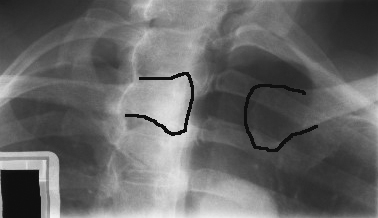

How is the patient positioned for a lateral sternum (erect)?

Arms and shoulders drawn back, chest out; mid-coronal plane perpendicular to IR.

Where is the CR for lateral sternum?

Perpendicular to mid-sternum, midway between jugular notch & xiphoid.

Why use increased SID (152–183 cm) for lateral sternum?

To reduce magnification caused by large OID.

What indicates correct positioning in lateral sternum?

Sternum free of rib/shoulder overlap, sharp bony detail, superimposed anterior ribs.